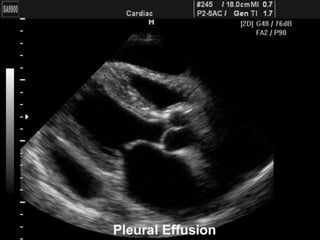

ECOGRAFIA TORAXICA

   Su mayor utilidad se basa en la localización de

derrames pleurales pequeños o encapsulados

consolidación.

   Permite detectar derrames muy pequeños (hasta 10

ml).

   Masas pleurales.

   En casos de dudas de engrosamientos o derrames

pleural.

   Guía para realizar la toracocentesis

http://es.scribd.com/doc/36096227/DERRAME-PLEURAL-I